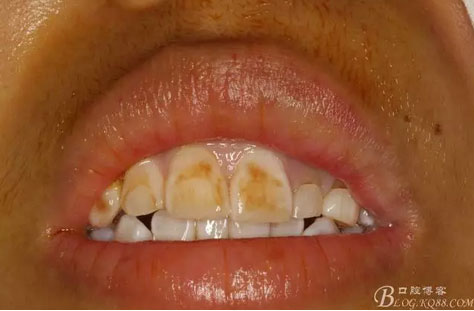

圖2.術前口內像,左側乳Ⅱ、Ⅲ滯留,頸部楔形缺損,探針不敏感。左側乳Ⅱ、Ⅲ唇側粘膜膨隆,表面結節(jié)狀,捫診質地堅硬,無波動。